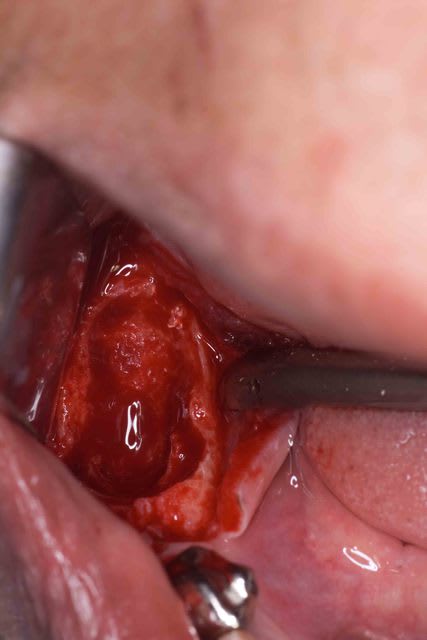

Bien vu c'est une dysplasie osseuse classique mais le remaniement a percé la crête osseuse et elle fait cellulites sur cellulites.

D'ou une petit chir pour retirer les "morceaux" et refermer de manière étanche.